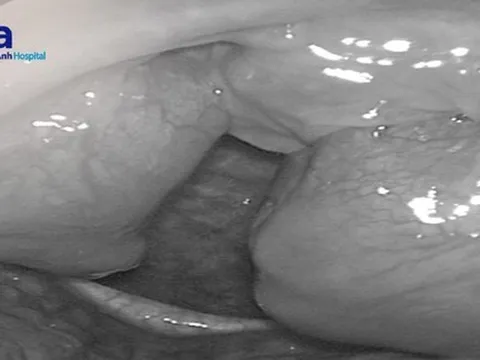

Người đàn ông có viên sỏi kích thước 6cm trong bàng quang

Trung tâm Y tế huyện Yên Lập (Phú Thọ) vừa phẫu thuật thành công trường hợp có sỏi bàng quang lớn bằng kỹ thuật tán sỏi ngược dòng.